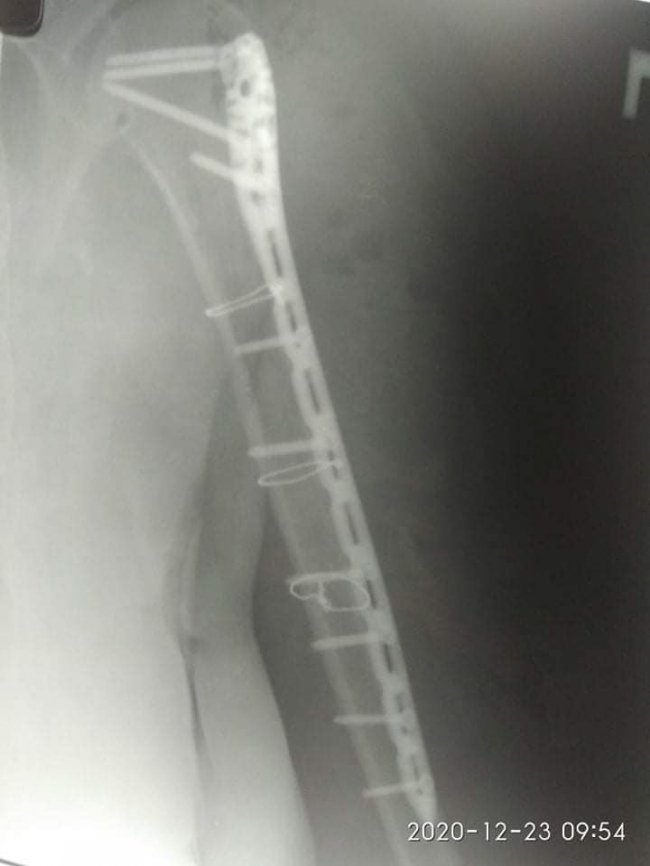

21 грудня їй провели 4-ьох годинну операцію – остеометалосинтез правої плечової кістки за допомогою LCP проксимальної Philos пластини та гвинтів.

Операція пройшла у складі лікарів-травматологів: Лотоцького І.А., Радчука В.М, Босого Т.Б..